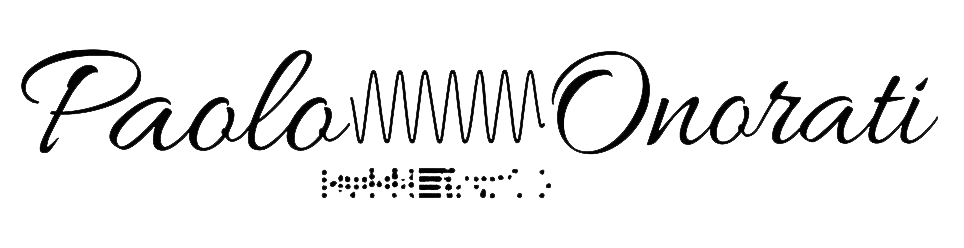

Analisi Statistica delle Mappe Topografiche dei Potenziali Evocati Somatosensoriali a Breve Latenza in Soggetti Normali e Parkinsoniani

- Integrare l’analisi temporale (picco N30) con la mappatura topografica nello spettro di potenza dei potenziali evocati somatosensoriali a breve latenza (SEP) registrati in soggetti parkinsoniani e in soggetti di controllo normali.

- Analizzare con un nuovo approccio statistico le differenze topografiche tra i due gruppi nei domini del tempo e della frequenza

L’obiettivo principale era identificare con maggiore precisione la topografia delle aree frontali del cuoio capelluto dove l’ampiezza dell’onda N30 risultava significativamente ridotta nei soggetti parkinsoniani.

La procedura statistica si è basata sull’uso combinato dell’analisi descrittiva dei dati (DDA) e dell’analisi multivariata, utilizzando una versione migliorata della Significance Probability Mapping (SPM) per valutare dati omo e NON omoschedastici con test parametrici.

Le differenze tra i gruppi sono state valutate con il Test Multivariato Hotelling’s T² e il relativo Test Post Hoc. Questo approccio ha permesso di determinare che le differenze statisticamente significative tra i gruppi, sia nel dominio temporale che in quello dello spettro di potenza, erano localizzate unicamente nelle aree frontali mediali e controlaterali del cuoio capelluto.